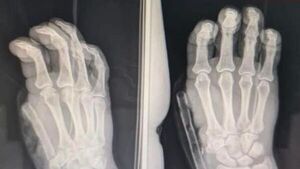

IPS REALIZA EXITOSA CIRUGÍA DE PULGARIZACIÓN DEL DEDO ÍNDICE A PACIENTE CON AMPUTACIÓN TRAUMÁTICA - Itapúa Noticias

Un paciente de 57 años tuvo una amputación traumática del primer dedo de la mano derecha tras recibir un impacto de proyectil de escopeta e ingresó al Hospital Central del Instituto de Previsión Social (IPS) donde se le practicó una cirugía al hombre t... [Leer más]

IPS realiza exitosa cirugía de pulgarización del dedo índice de la mano derecha - .::Agencia IP::.

Asunción, Agencia IP.- Un paciente de 57 años tuvo una amputación traumática del primer dedo de la mano derecha tras recibir un impacto de proyectil de escopeta e ingresó al Hospital Central del Instituto de Previsión Social (IPS) donde se le practicó ... [Leer más]

Perdió el pulgar por un escopetazo y médicos de IPS le transfirieron otro dedo en su lugar - Nacionales - ABC Color

Médicos del Hospital Central de IPS realizaron una cirugía de pulgarización del dedo índice de la mano derecha a un hombre de 57 años que sufrió una amputación del pulgar de dicha mano. El paciente, oriundo de San Juan Bautista, Misiones, recuperará la... [Leer más]

La increíble transformación de un dedo pulgar amputado

En IPS Central se logró extender el dedo índice de la mano. "Ahora está súper feliz", afirmó uno de los médicos traumatólogos. [Leer más]

Crónica / Le reemplazaron el dedo, en el lugar del pulgar le colocan el índice

Un hombre de 57 años a quien el impacto de una bala le destrozó el dedo pulgar de la mano derecha, fue sometido a una cirugía en el IPS en donde le [Leer más]

IPS: Pulgarizan con éxito el dedo índice de un hombre

Profesionales del Hospital Central de IPS realizaron con éxito una compleja cirugía de pulgarización de un dedo índice en la mano derecha de un paciente, lo que permitirá que el mismo pueda recuperar la funcionalidad de su miembro. [Leer más]

Exitosa cirugía de pulgarización del dedo índice de la mano derecha.

Un paciente de 57 años tuvo una amputación traumática del primer dedo de la mano derecha tras recibir un impacto de proyectil de arma de fuego. [Leer más]